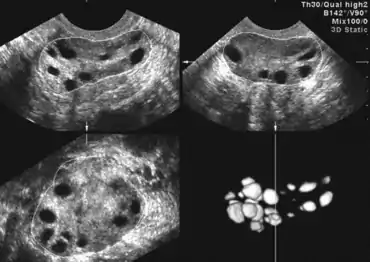

Яєчники при синдромі можуть містити від декілької кіст до більш ніж 20-ти. Коли в фолікулах яєчників утворюються множинні кісти внаслідок гормонального дисбалансу, це характеризується як СПКЯ. Через утримуваних у воді кіст, деякі з яких можуть досягати 10 мм в ширину, розмір яєчника збільшується до 10 см в ширину. Відсутність овуляції і менструального циклу перешкоджає заплідненню і зачаттю, тому вагітність стає важкою.